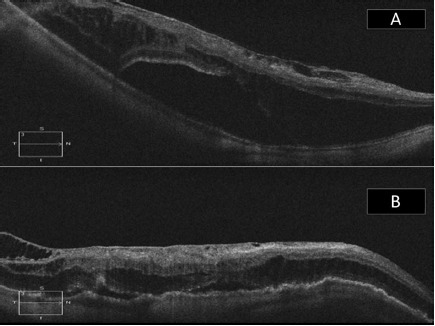

8.png

图 7 A 为后巩膜葡萄肿黄斑脱离合并裂孔患者术前 OCT,视网膜前膜表现为中心凹外的切向牵引力;B 为同一只眼术后 2 年,视网膜 - 脉络膜 - 巩膜在扣带处完全变平,黄斑脱离恢复且无切向牵引力(扣带组)

7.png

图 8 A 为眼眶 T2 TSE 轴 MRI,双眼球后部黄斑及乳突葡萄肿畸形;B 为同一只眼扣带术后 1 月 MRI,右眼球后壁变平;C 为另一患者眼眶 T2 TSE 轴 MRI,双眼球后部黄斑及乳突葡萄肿畸形,从底部观察到左眼有一黄斑脱离;D 同图 C 为同一只眼,扣带术后 1 月 MRI,左眼眼球后壁扣带处轻微突起。